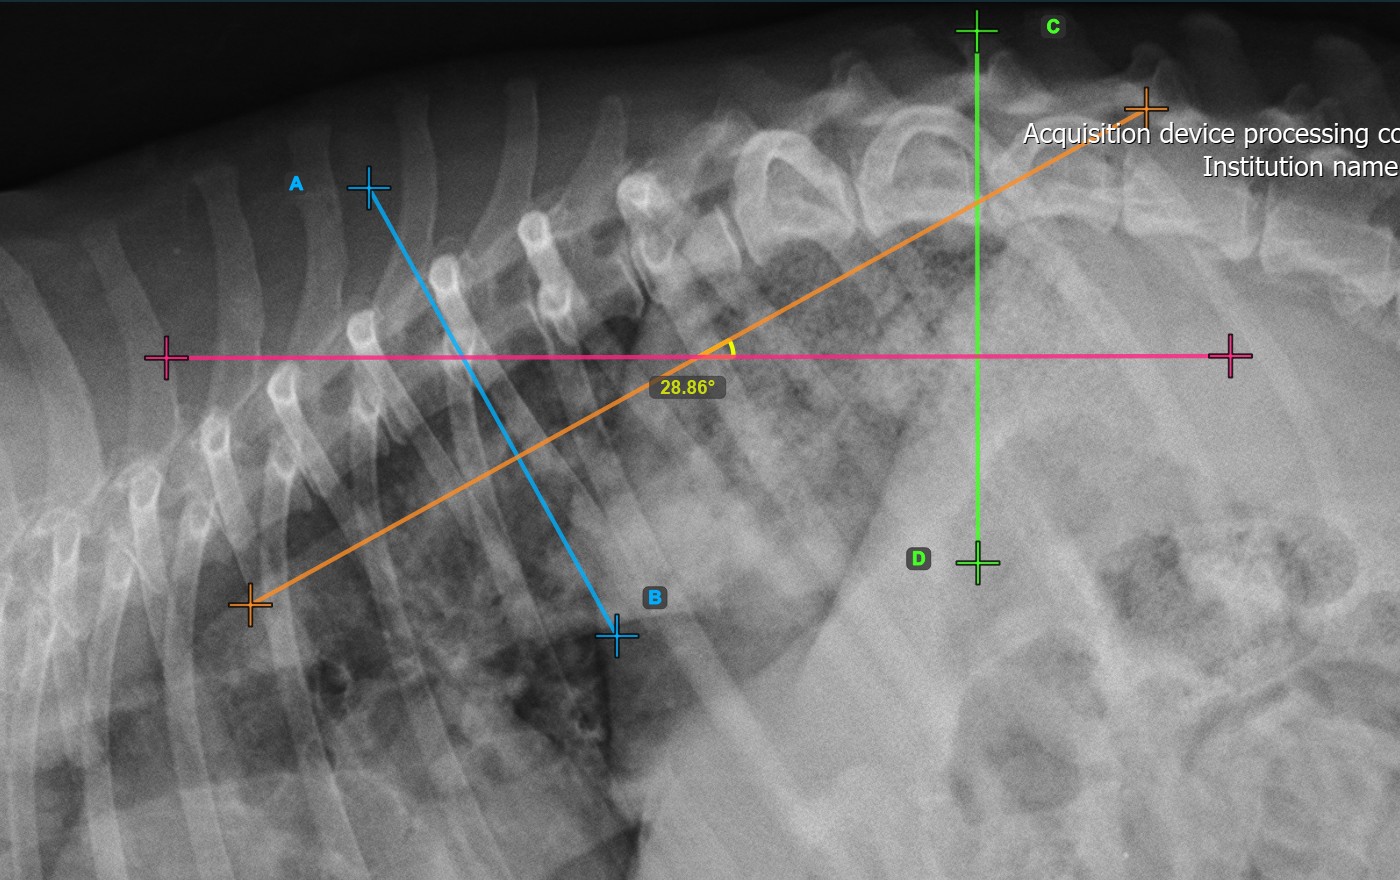

Mark the second vertebral line on the spine to calculate the deformity.

Identify the vertebral endplate at the opposite end of the largest spinal curve deformity. Place the start and end point of the second vertebral line precisely along the identified endplate. Adjust each point on the scene to better align the line with the endplate if needed.

The Cobb Angle measurement will be automatically calculated and completed once the two vertebral lines are placed, indicating the angle of spinal curviture in degrees.

The image below represents a typical placement of the second vertebral line.

Modify the position and orientation of the two vertebral lines to automatically recalculate the Cobb Angle.